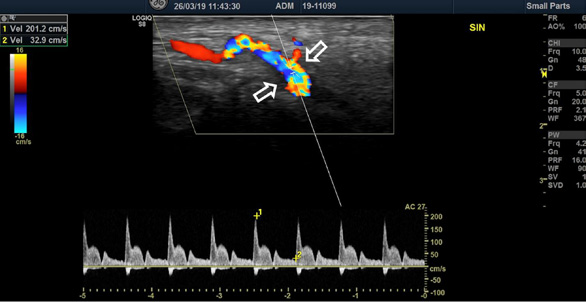

Five years later, at the follow-up visit, the patient did not feel any pain or discomfort in the temporal area bilaterally. No inflammatory signs of temporal arteries were detected (Fig. 3). The control color-coded duplex sonography showed no halo sign, and normal blood flow velocities were registered (Fig. 4). It was concluded that there were no clinical or ultrasound signs of temporal vasculitis.

Fig. 4. Color-coded duplex sonography of superficial temporal artery after the treatment (2024)

Normal blood flow velocities of the right (A) and left (B) superficial temporal arteries were observed without the ‘halo’ sign.